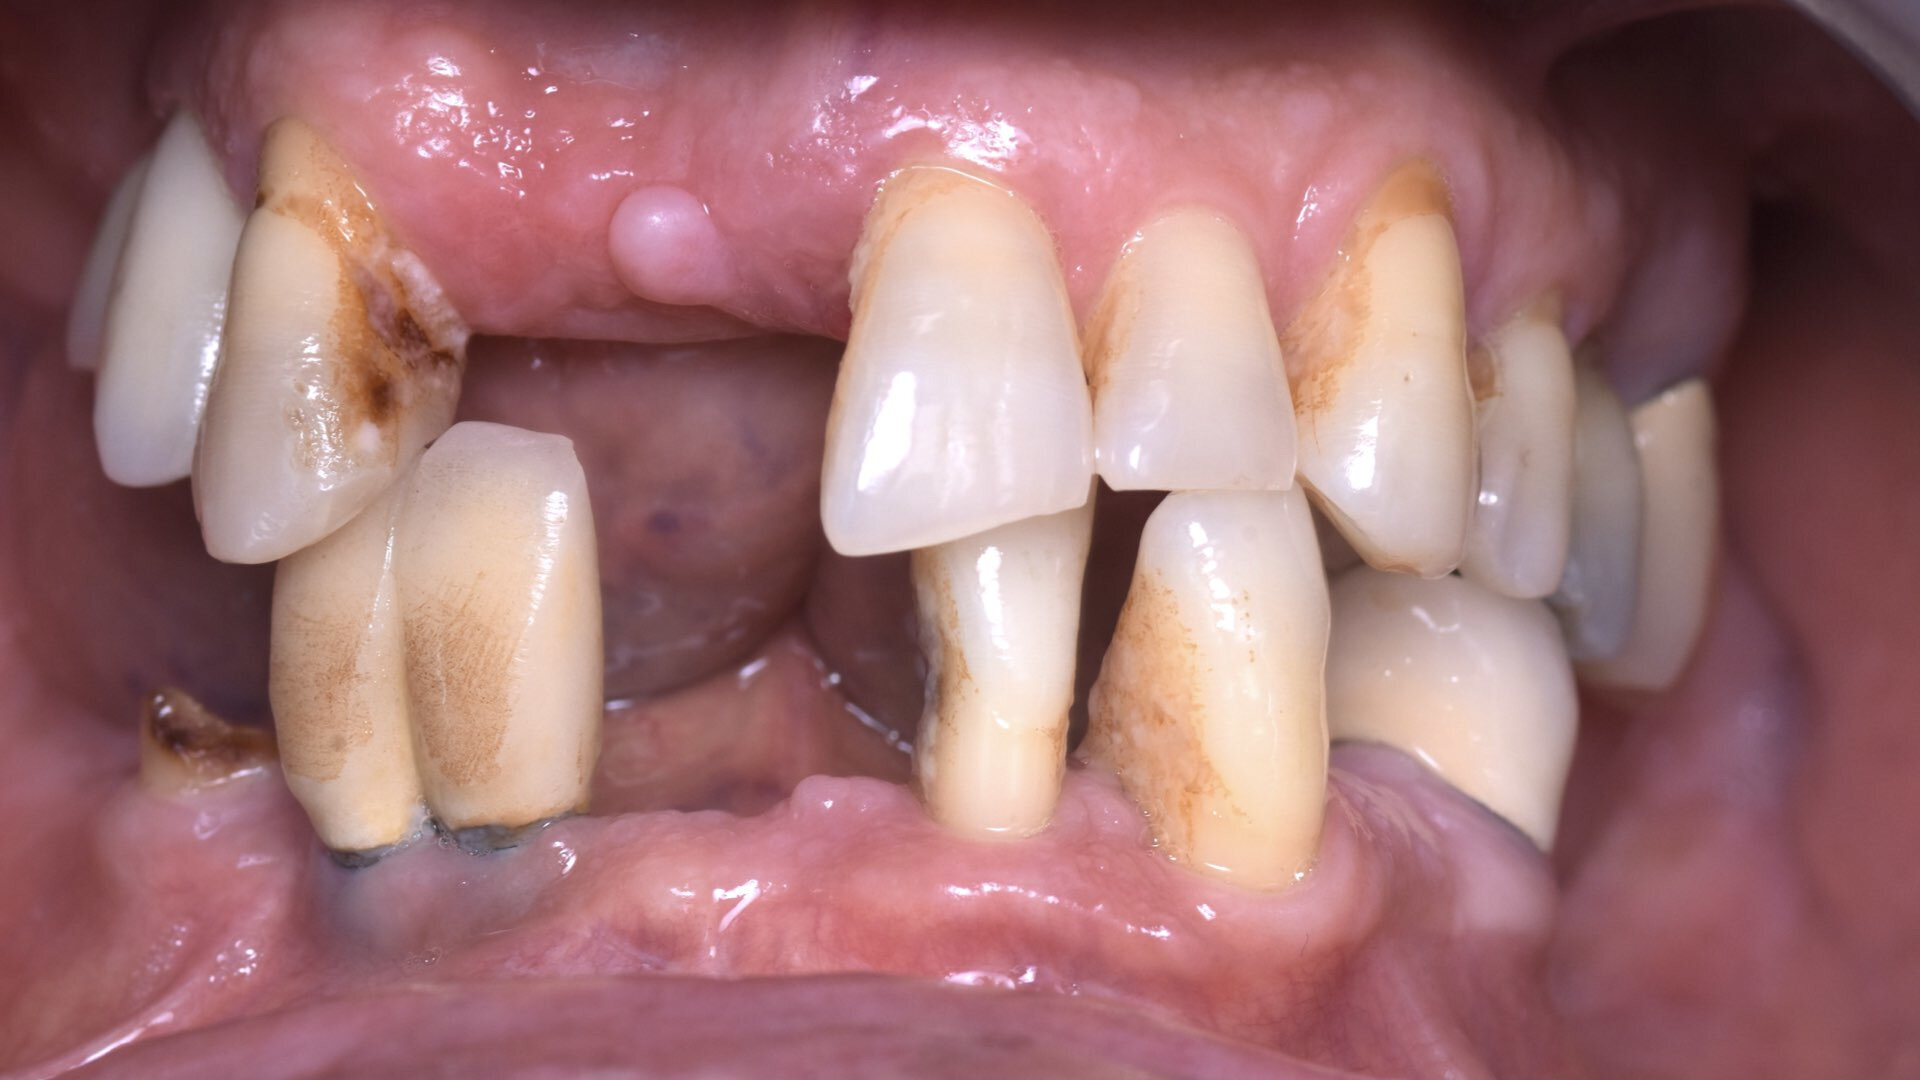

La radio panoramique (Fig. 15), quant à elle, nous montre une uniformité dans la répartition de la position des implants, ainsi qu’une connexion pilier conique-implant de type cône morse du All-on-4 au maxillaire, ce qui assure une étanchéité nécessaire à des implants posés en position infra-osseuse. Nous observons un cas classique de réhabilitation par quatre implants verticaux à la mandibule.